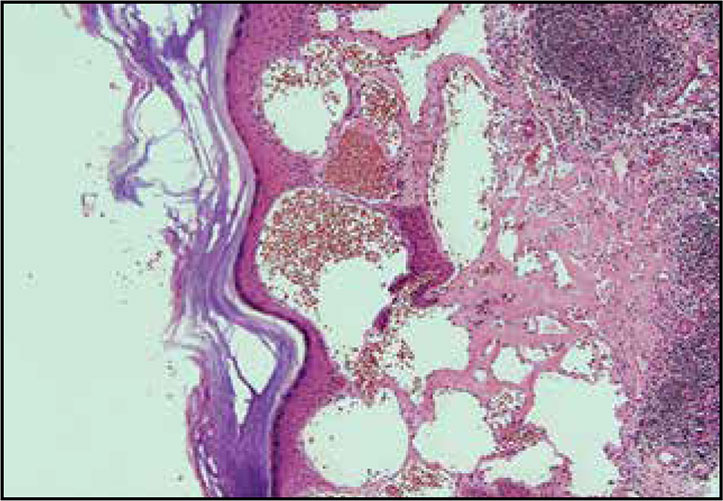

El angioqueratoma nevoide circunscrito es el más raro de los cinco tipos de angioqueratomas descritos en la literatura. Estas lesiones usualmente están presentes al nacimiento y no se relacionan con enfermedad sistémica.

Presentamos el caso de un hombre de 32 años con cuadro clínico de angioqueratoma nevoide circunscrito tratado con crioterapia, con buena respuesta inicial.